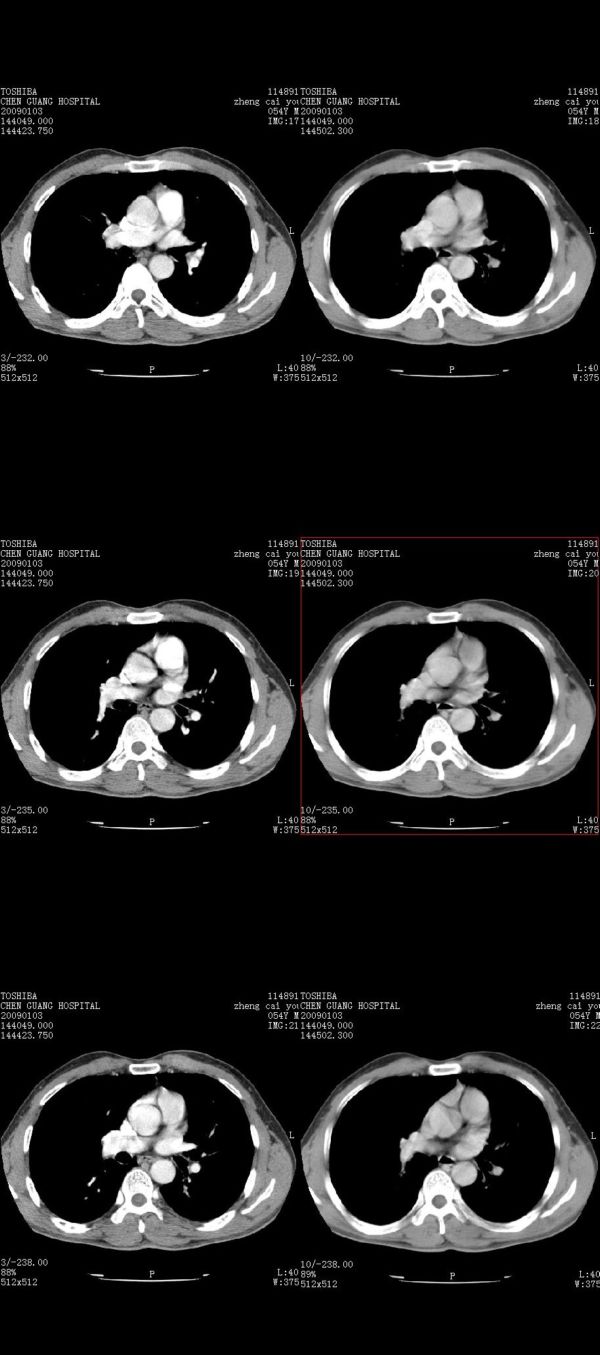

男,54岁,右侧胸部疼痛,平时吸烟,有抽烟后咳嗽咯痰史。昨天没把xiphoid软件吃懂,所以没把纵隔窗图像处理出来!请各位老师帮忙看一下右肺门有没有问题?谢谢!!!!!!!!!!

右肺上叶后段近气管旁仍可见一结节灶,不除外为肿大的淋巴结影。

我同学讲红线部分强化不好,感觉不是很舒服,这是什么道理?

我同学讲红线部分强化不好,感觉不是很舒服,应该 是软组织间隙,不是一个孤立的病灶。

气管前腔静脉后似见增大淋巴结影,肺门区未见明显肿块影。肺窗示右肺中叶外侧段透亮度增高,可过一段时间再查一下对比一下,毕竟是自己的至亲,又有条件,辐射就顾不得了。

也觉得还好吧,只是右下肺动脉显粗了点,纵膈有钙化淋巴结,再有肺窗就更好了

各位老师:奇静脉增宽,肺上未见明显实变,这还需注意观察些什么?????

右侧肺门影增大,不除外增大淋巴结可能